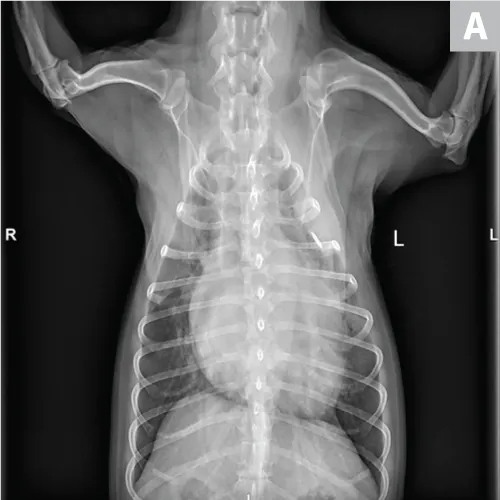

Pulmonary neoplasia may, on occasion, have a more diffuse nature. This is common with pulmonary lymphoma40 and is sometimes seen with carcinoma (author experience). Pulmonary lymphoma can have a rapid clinical course and mimic acute disorders. A diffuse, unstructured interstitial pattern is typically appreciated. Additionally, bronchointerstitial, alveolar, and nodular patterns may be observed (Figure 7).40

FIGURE 7

(A) Pulmonary lymphoma with a diffuse, patchy bronchointerstitial pattern confirmed on bronchoalveolar lavage and peripheral lymph node aspiration. (B) Pulmonary carcinoma with a diffuse, severe bronchointerstitial pattern confirmed on bronchoalveolar lavage and postmortem examination. Note: Pulmonary and hilar lymphadenopathy are not always present.

Diagnosis of pulmonary lymphoma requires airway cytology, pulmonary fine-needle aspiration, and/or confirmation on nonpulmonary samples.41